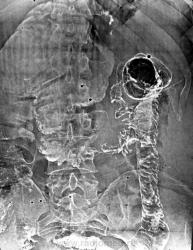

Рак поперечной ободочной кишки. Расширение правой половины толстой кишки до 10-12 см максимум, хотя может быть и больше (вот вам и "приводящая петля"....). Кстати, как вам понятие "частичной" кишечной непроходимости, имеет ли оно право на жизнь?

Этот диагноз сам собой просится как наиболее вероятный. А видит ли коллега в этой скудной картине что-то, что не позволяет сомневаться в таком диагнозе?

Прежде всего характер самого сужения: протяженность, неровные контуры, патологическая перестройка рельефа, подрытые края...что еще, недоступное моему глазу утаилось....признавайтесь, что увидели, Петрович?

У меня, Виктор Григорьевич, опыт ирригоскопии, очевидно значительно меньший. Перестройка рельефа, да, но на всём протяжении он какой-то «одинаковый», подрытые края на мой взгляд не очевидны. Не хватает мне явной «злокачественности».

Очевидно, стойкое сужение просвета поперечно-ободочной кишки. Рельеф тут который-то непонятный… воздухом бы раздуть.

Рак поперечной ободочной кишки. Расширение правой половины толстой кишки до 10-12 см максимум, хотя может быть и больше (вот вам и "приводящая петля"

....). Кстати, как вам понятие "частичной" кишечной непроходимости, имеет ли оно право на жизнь?

Прежде всего характер самого сужения: протяженность, неровные контуры, патологическая перестройка рельефа, подрытые края...что еще, недоступное моему глазу утаилось

Что-то длинновато для рака. Сдавление / прорастание со стороны брыжейки? У меня был похожий случай с лимфосаркомой брыжейки